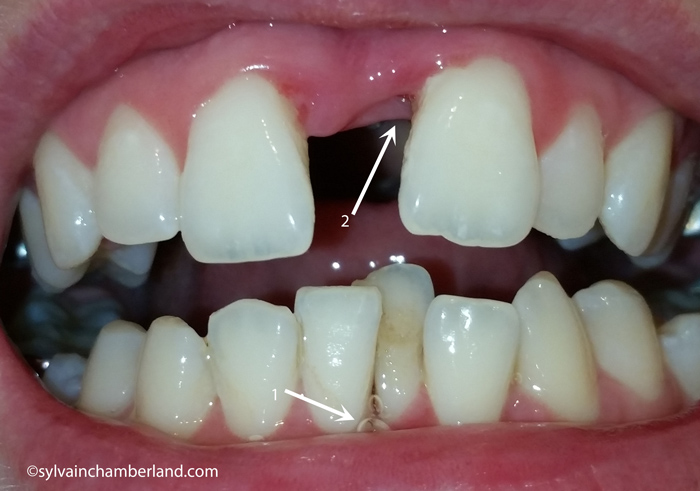

Cette autre photo à droite présente une guérison inachevée entre les incisives supérieures. La flèche 1 indique une possible récession de gencive entre les incisives centrales inférieures.

La flèche #2 indique une cavité au mésial de l’incisive centrale supérieure gauche qui correspond à la flèche #3 sur la radiographie panoramique. La flèche #2 sur la photo et la flèche #3 sur la radio confirme l’absence d’ossification au mésial de l’incisive. Je serais curieux de savoir s’il y a un attachement du ligament ou s’il y a une poche profonde. Je gagerais sur une poche profonde. Cela n’est pas de bon augure. Je souhaite que tout entre dans l’ordre pour vous. Il me semble évident qu’il y a eu une fracture asymétrique du septum interincisif supérieur où tout l’os est demeuré sur la dent de droite et aucun sur la dent de gauche. J’avoue craindre pour votre incisive supérieure gauche. Des soins particuliers seront nécessaires pour obtenir une guérison osseuse entre les 2 incisives.